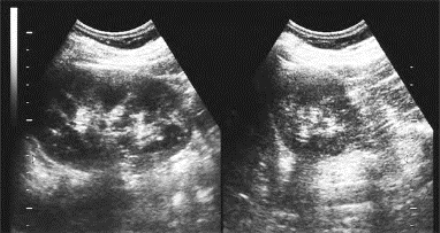

(1)肾动脉及肾静脉的肾外部分在二维超声或彩色多普勒超声均可显示(图29-4)。

图29-4 正常肾血管声像图

图A示左、右肾动脉及左肾静脉;图B示左肾静脉及下腔静脉

(2)肾脏内部血管各级分支可用彩色多普勒超声显示,在侧腰部冠状切面上,肾动脉各级分支显示红色血流,肾静脉支呈蓝色血流。